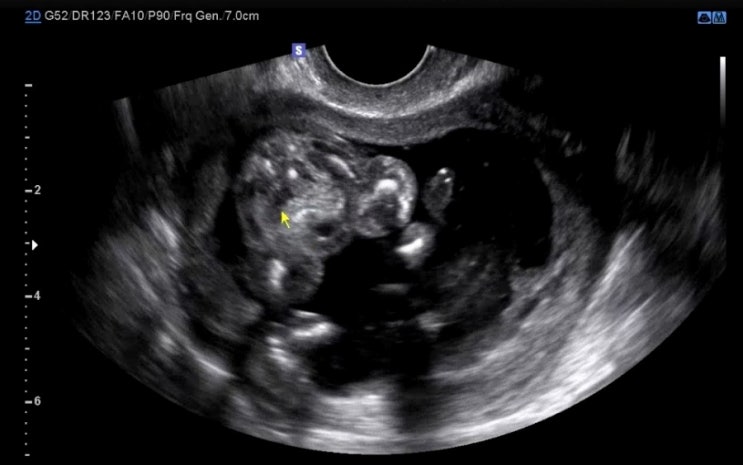

[임신 일기] 딱복이? 두구두구두구 성별을 공개합니다 (임신16주) / 1,2차 기형아검사 통과, 배뭉침

입덧이 말끔히 나아지진 않았지만 체한 느낌과 울렁거림을 잘 다스려가며 입덧약 한알로 하루를 보내는 16...